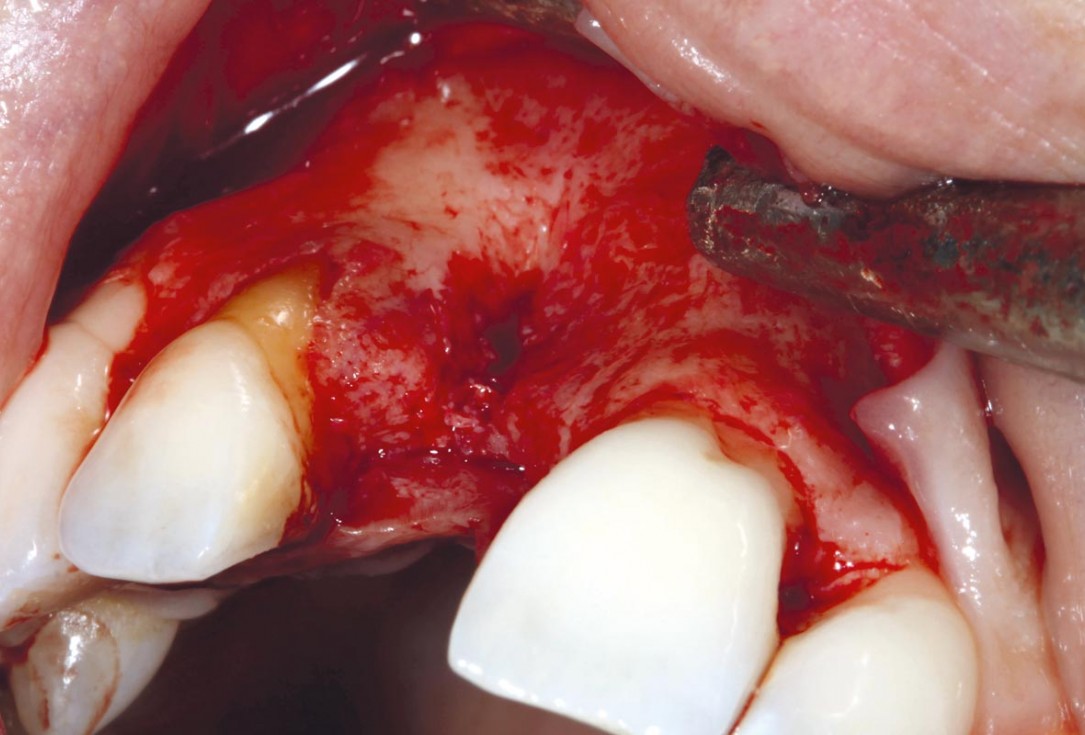

1/11 - Clinical situationmaxgraft® cortico at combined defect palatally and facially - Dr. K. Höckl

Situation after tooth removal.